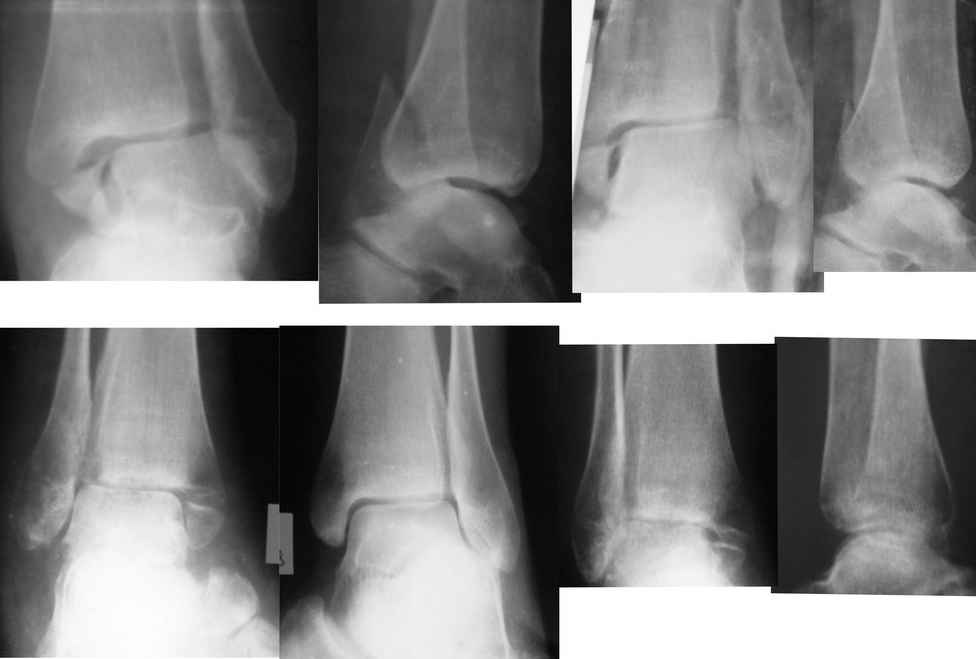

Re: Застарелый перелом лодыжек

Gennady Tenison 07 Май 2010, 14:35

Евгений!. Вы сами ответили на вопрос. Оперировать безусловно, восстановить длину малоберцовой кости, позиционный винт и винты на внутреннюю лодыжку. Послеоперационное ведение как при свежем переломе, отсчет от дня операции, о потерянных двух месяцах придется больной забыть.

Отправитель: Андрей Волна 07 Май 2010, 23:33

Да, абсолютно точно, Геннадий Вильгельмович. Разделяю Ваше мнение.

Единственное, в таких случаях более мощную пластину взамен классической 1/3 трубки предпочитаю выбирать. Или переходную метафизарную, что дороже. Или реконструктивную. Что бюджетнее.

Дедок Михаил 07 Май 2010, 23:11

Оперировать + ранее функциональное лечение.

Евгений 08 Май 2010, 00:24

Уважаемые коллеги, спасибо за помощь. Подберём более мощную пластину (есть в наличии малоконтактные). Фрагмент внутренней лодыжки небольшой, думаем синтезировать спицами и проволочным серкляжом.

Бережной Сергей 08 Май 2010, 00:57

Проволочный серкляж для внутреней лодыжки приведет к значительно большей травматичности вмешательства. Вполне можно обойтись 2 спицами или спицей и винтом. Все-таки основное внимание должно быть уделено наружной лодыжке. И, учитывая имеющийся регионарный остеопороз, лучше пусть будет более тонкая блокируемая пластина, чем мощная без возможности блокирования.

ANDREW 08 Май 2010, 02:33

А в чем вы видите большую травматичность при остеосинтезе по Веберу внутренней лодыжки? По-моему в предстевленном случае остеопоротические изменения могут привести к разлому лодыжки при остеосинтезе, а фиксация по Веберу даст не меньшую стабильность.

Бережной Сергей 08 Май 2010, 02:56

Большая травматичность при остеосинтезе по Веберу определяется необходимостью обнажения проксимальной части лодыжки для проведения проволоки. И неплохо было бы запланировать какую-нибудь стимуляцию остеогенеза на такое вмешательство. Дешевле и эффективнее взять с крыла подвздошной кости. Но это на вкус хирурга.

Бережной Сергей 08 Май 2010, 21:33

На рекомендованном Вами рисунке как раз отлично видна большая травматичность вмешательства в сравнении с остеосинтезом 2 спицами или спицей и винтом.

Александр А. 09 Май 2010, 00:38

Безусловно операция необходима. Думаю после востановления латерального компонента составляющей сустава, в сопоставлении медиальной лодыжки проблем не будет, а фиксация (каким способом лучше владеете), если уж хочется совсем малоинвазивно - канюлированные компрессирующие винты, а вобще думаю абсолютно не имеет значение разрез 3см или 3см3мм.

Вот только исходя из личного опыта считаю, что через два месяца после травмы позиционного винта на синдесмоз будет мало, не обойтись без старого доброго болта-стяжки, (по крайней мере у меня не получалось, это не свежая травма). Тем более послеоперационный период предполагается без внешней иммобилизации с ранним включением функции.